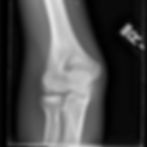

The next appropriate step in management is to obtain an elbow x-ray.

Preference for initial x-ray evaluation is at least a 3 view elbow x-ray including AP, lateral, and external oblique.